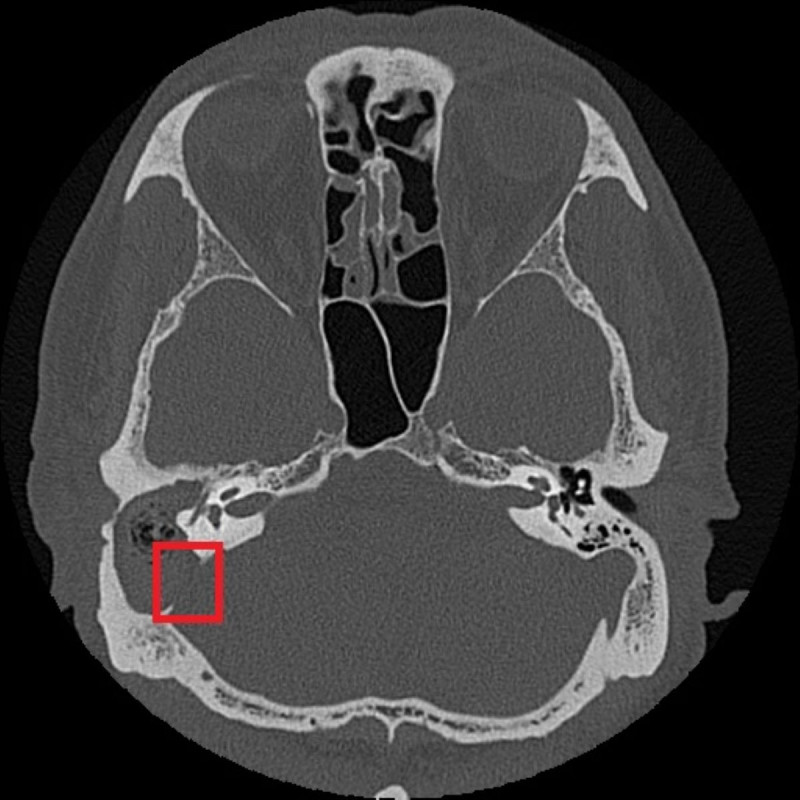

慢性中耳炎勿輕忽 併發膽脂瘤造成聽力與神經損傷

75歲張先生右耳曾罹患慢性中耳炎並合併耳聾,近日右耳出現耳痛、耳脹並伴隨膿性分泌物,於診所治療未見改善,轉至醫院耳鼻喉科就診檢查發現外耳道嚴重紅腫狹窄,內部堆積大量碎屑及...…